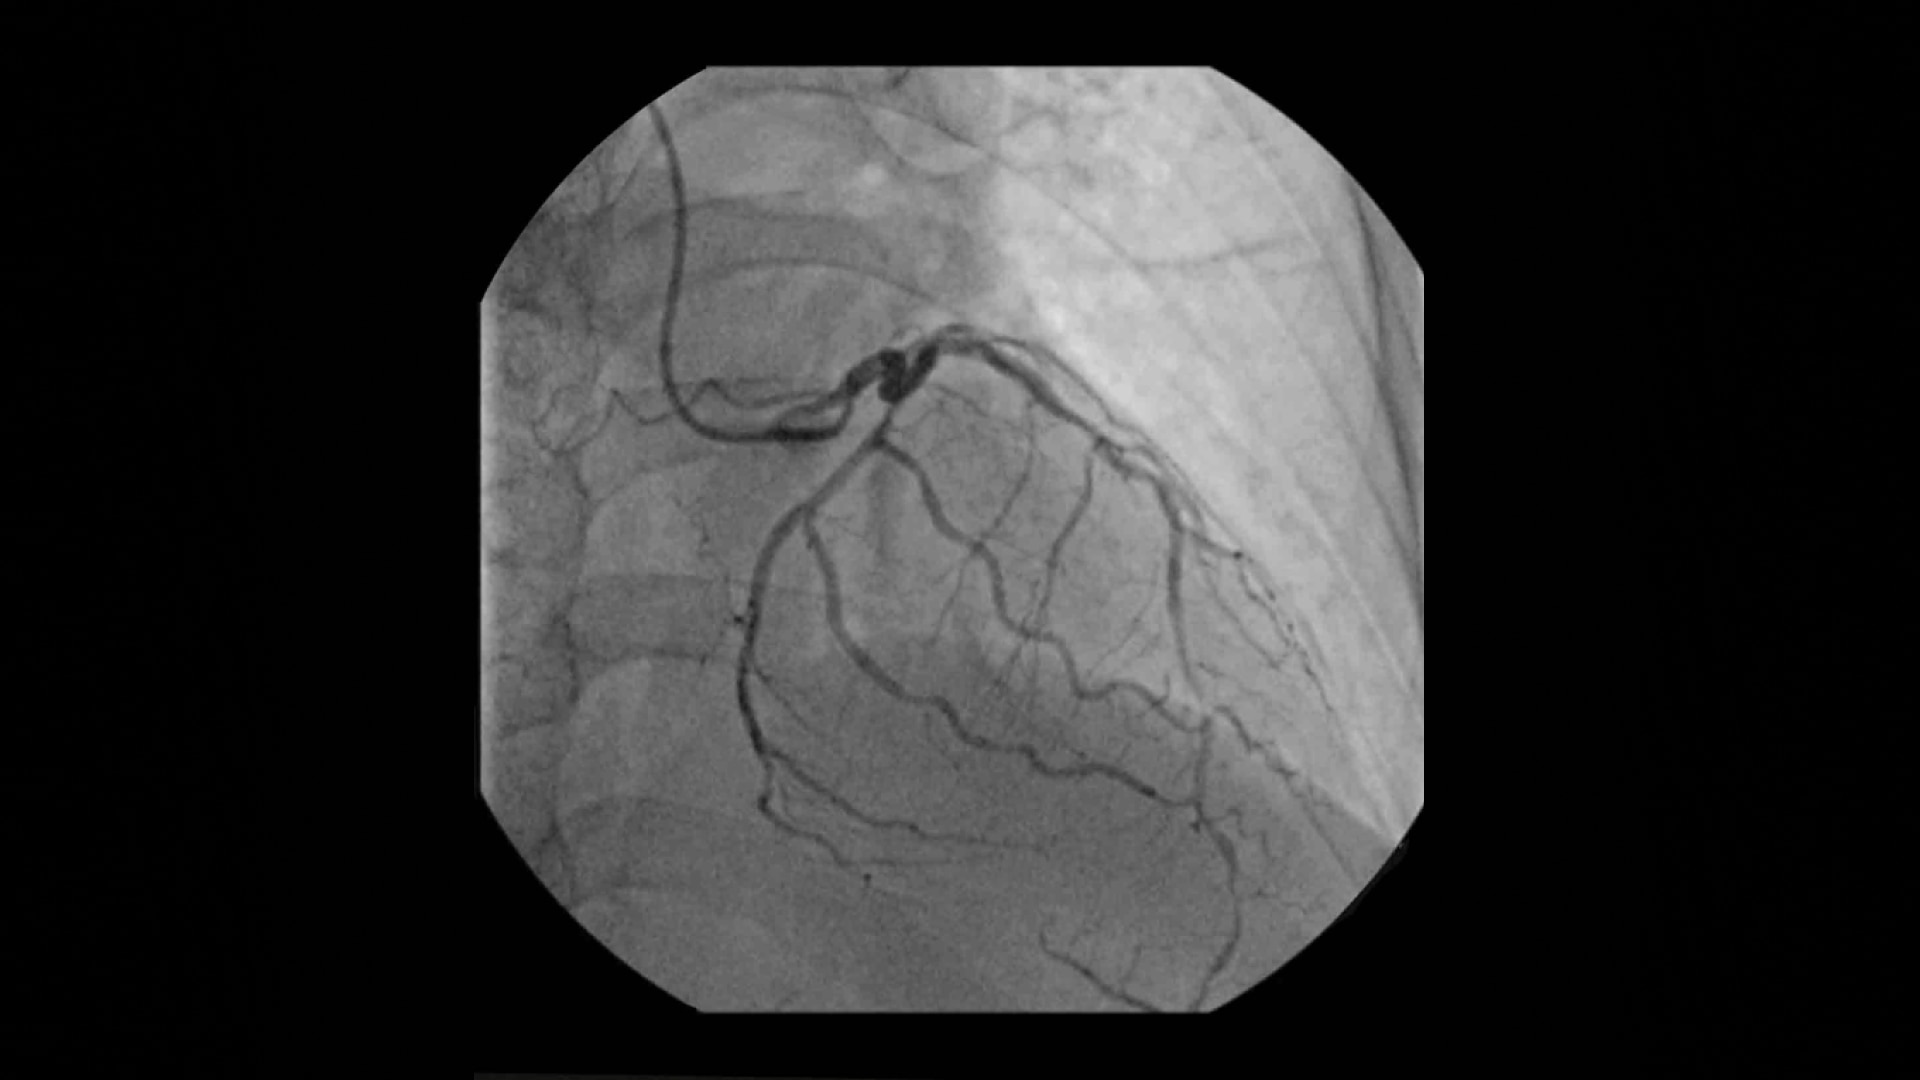

Bei der Platzierung von Schrittmachern liefert der OEC Elite CFD mit Flachdetektor, fortschrittliche Bildverarbeitung und einen hochauflösenden 4K-Display, sowie eine außergewöhnlich klare Darstellung – selbst von kleinsten 0,014" Führungsdrähten im Thoraxbereich.

Das speziell entwickelte kardiologische Preset-Profil reduziert automatisch Überstrahlungsartefakte und ermöglicht die präzise Visualisierung beweglicher Instrumente wie Katheter und Stents in den Koronararterien.